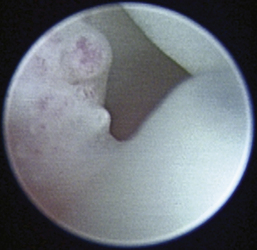

The normal vertical and horizontal ear canal should be pink, and in most animals, the cartilage is flexible; thus the otoendoscope should advance easily down the canal. There can be small amounts of wax in the ear canal. In animals with otitis externa, the changes detected in the ear canal are related to the severity of the ear disease. The first changes noted in the ear canals in cases of acute otitis externa include erythema and glandular hyperplasia (Figure 20-1). The amount of exudate in the ear canal is variable and should be documented, as should its color and consistency. A swab sample from each ear should be obtained for cytologic evaluation. If numerous rod bacteria are noted cytologically or the infection has worsened since the last visit, then a bacterial C/S is indicated. In more severe cases of otitis externa, glandular hyperplasia progresses, resulting in stenosis of the canal, sometimes to the point where the otoendoscope can no longer be advanced into the vertical ear canal. The degree of stenosis and hyperplasia should also be documented. Ulcerations may also be noted, especially in ears secondarily infected with P. aeruginosa. Parasites such as Otodectes cynotis may be visualized rapidly moving about in the ear canal with the video otoscope and are usually found in conjunction with dark brown ceruminous (“coffee ground”) exudate. On occasion, masses or foreign bodies may be seen in the ear canal during the video otoscopic examination.

image

Figure 20-1 Mild erythema and glandular hyperplasia associated with otitis externa are some of the first changes noted in the ear canal.

(Courtesy of Dr. Lynette Cole, The Ohio State University, Columbus, Ohio.)